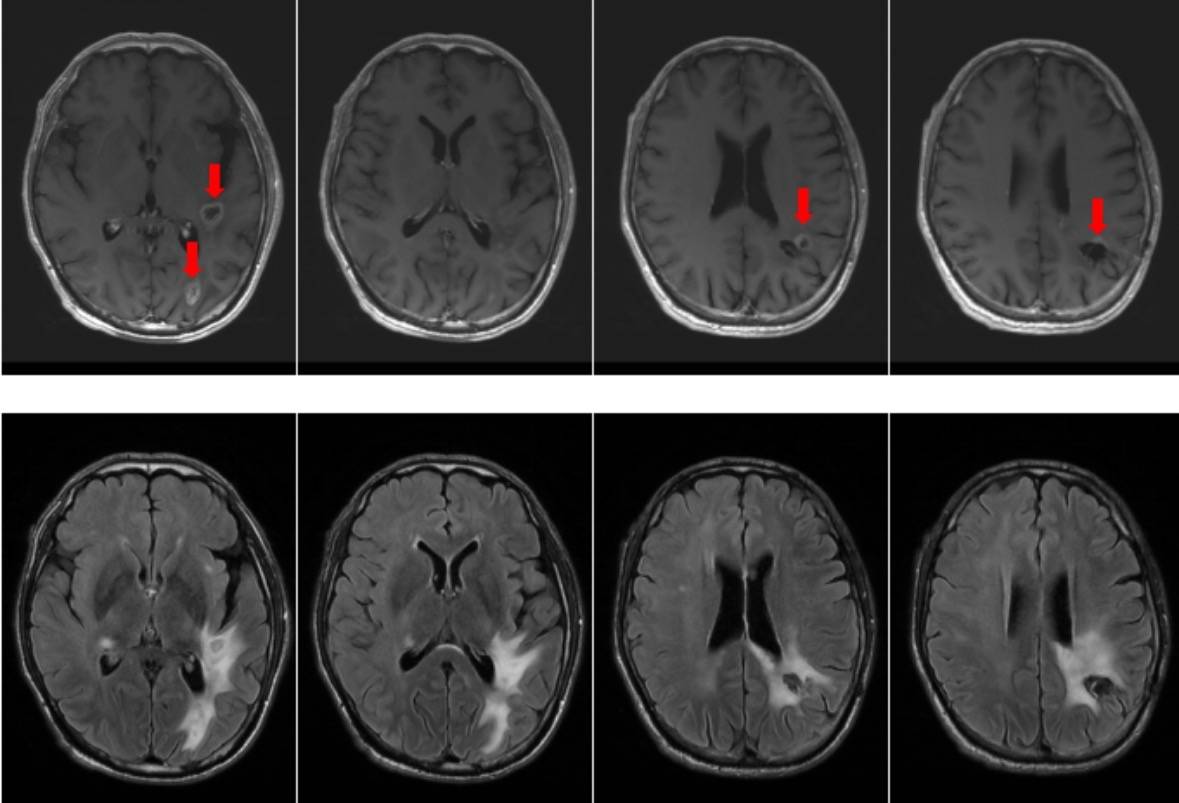

2025年08月21日患者开始于我科行化疗。治疗7周期后,2026年1月12日核磁显示颅内多发异常信号影较前增大并新增异常信号影,病灶周边水肿明显,见图2。

图2:2026-1-12头核磁显示颅内多发异常信号影较前增大并新增异常信号影,病灶周边水肿明显。

故2026年1月14日起更换靶向联合免疫治疗方案为:贝伐珠单抗+卡度尼利单抗,化疗2周期后,2026年2月26日核磁显示颅内多发异常信号,较前片缩小,周围水肿减轻(图3)。治疗期间患者未出现新增症状及明显不良反应。目前患者仍在继续治疗中。

图3:2026-2-26头核磁:颅内多发异常信号,较前片缩小,周围水肿减轻。